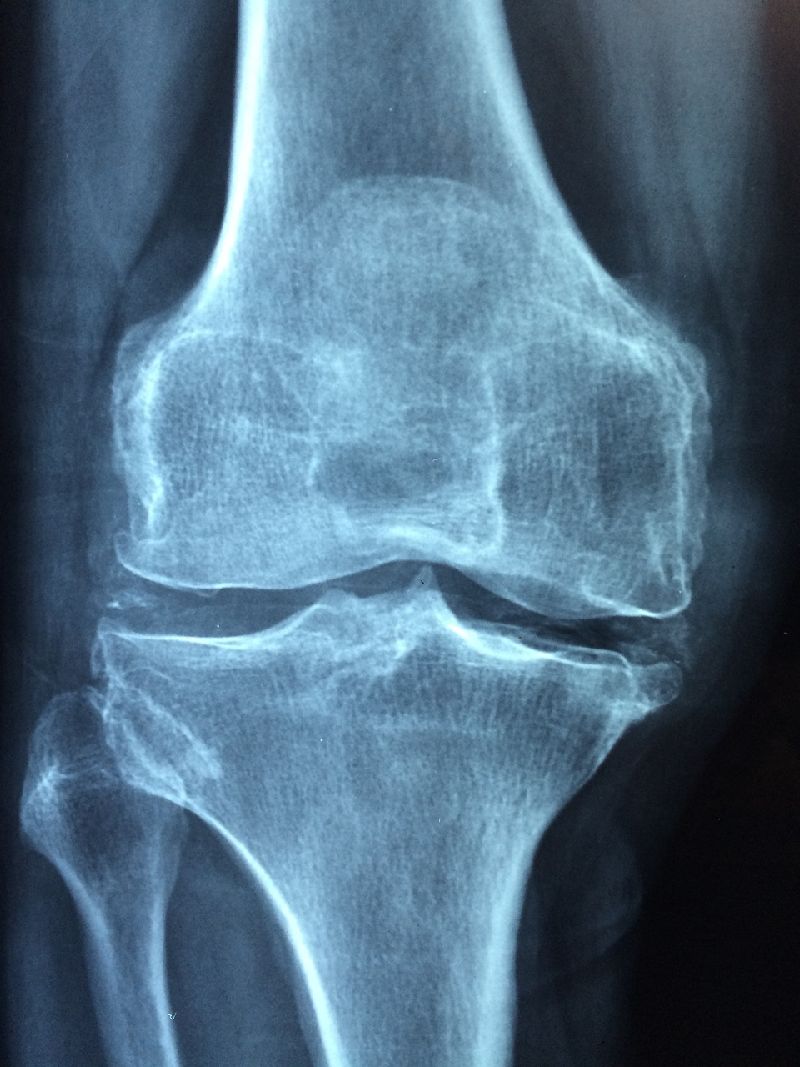

콘드로이친은 인체에서 자연적으로 발생하는 물질로, 주로 연골에서 많은 양이 발견됩니다. 콘드로이친은 관절 건강을 개선하고 관절염이나 관절 통증을 예방하는 효과가 있지만, 나이가 들수록 체내 함량이 감소하는 단점을 가지고 있습니다.

콘드로이친은 골관절염에 의해 나타나는 여러가지 통증과 불편함을 완화하는 효과가 있습니다. 또한, 뛰어난 항염증 작용을 가지고 있습니다. 관절에 발생하는 염증과 붓기를 완화하는데 도움이 됩니다.[골괄전염이란?]

2.3 연골 보호

콘드로이친은 연골을 구성하는 성분으로, 연골을 더 튼튼하게 만들고 보호하는 역할을 합니다. 연골에 대한 더 자세한 내용은 [여기]를 참고하시기 바랍니다. 한 연구에 따르면 콘드로이친을 복용한 환자들은 연골의 손실이 33% 감소했고, 연골의 밀도가 5.4% 증가했습니다.